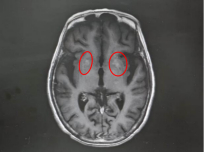

该院神经内一科副主任匡祖颖接诊后,详细询问了病史并进行查体,结合影像检查结果,迅速锁定了病因——非酮症高血糖性偏侧舞蹈症。影像显示,王奶奶的双侧基底节区出现异常信号,而进一步追问才知道,她两年前就查出高血糖,却一直没有规律服药,往往只在自我感觉血糖升高时才吃一点降糖药。这次入院后测出的空腹血糖高达13mmol/L,餐后血糖更达到21mmol/L,是正常值的两倍。匡祖颖解释,这种病多见于血糖控制不佳的人群,核心诱因正是长期严重的高血糖“烧坏”了大脑深部的纹状体。

纹状体是大脑基底节的关键组成部分,专门负责协调和控制人体的动作。当血糖长期处于严重升高状态,会持续损害这一精密调控区域,导致其功能紊乱、运动指令失控,进而出现单侧肢体甚至面部不自主的舞蹈样动作。这也就解释了为什么王奶奶从嘴角抽动逐渐发展到眼睛、脖子和手掌“停不下来”——她所表现出的,正是大脑运动协调区被高血糖持续损伤后发出的失控指令。